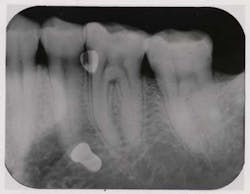

Fig. 1b — Periapical taken by hygienist reveals overcontoured No. 14 restoration that was resulting in a food trap and gingival inflammation.